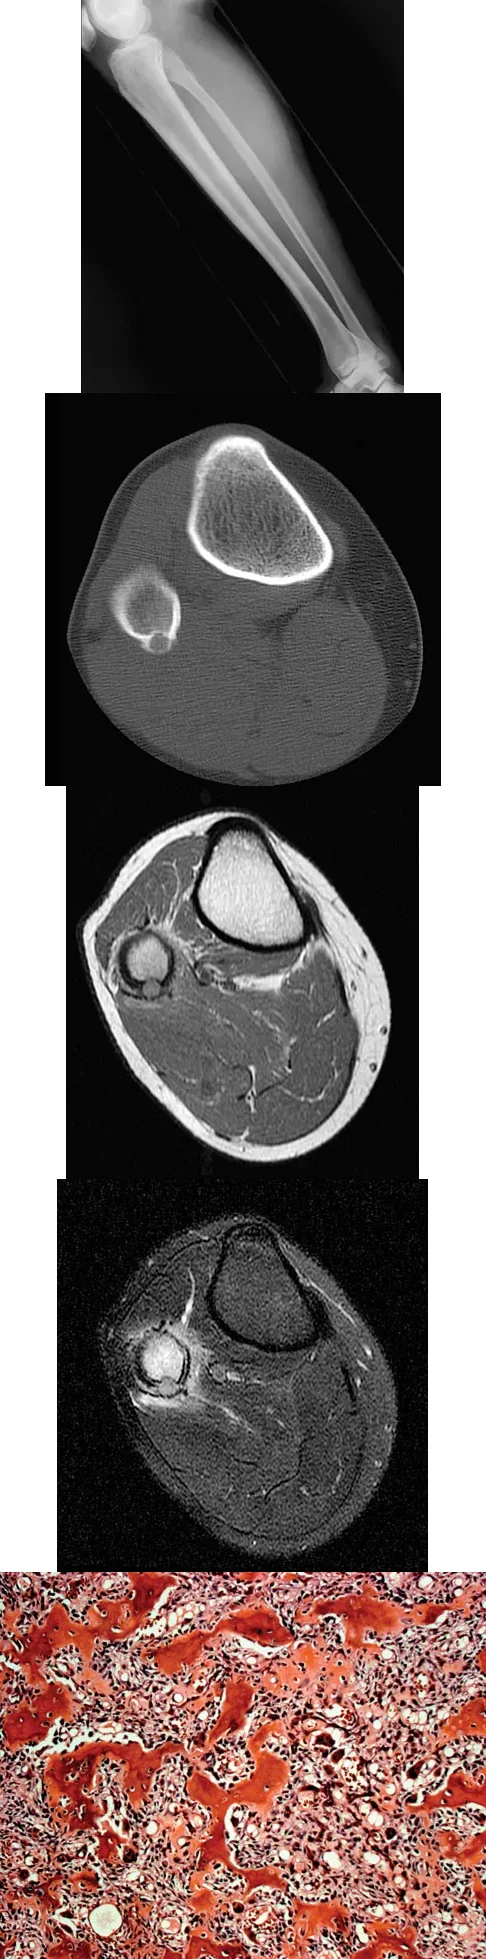

A 23-year-old man presents with right posterolateral knee pain, worse at night and relieved by NSAIDs. Imaging and histology are shown. The histologic specimen demonstrates a cellular, vascular stroma with plump osteoblasts producing immature woven bone. What is the currently preferred minimally invasive treatment for this lesion?

Explanation

Correct Answer: B

The clinical presentation, imaging (cortically based lytic lesion with surrounding sclerosis/edema), and histology (vascular stroma with osteoblasts and woven bone) are classic for an osteoid osteoma. Percutaneous radiofrequency ablation (RFA), typically under CT guidance, has become the preferred treatment method, offering high success rates with minimal morbidity compared to open surgical excision.

A 23-year-old man presents with right posterolateral knee pain that is worse at night and dramatically relieved by NSAIDs. Imaging reveals a well-circumscribed, cortically based lytic lesion in the proximal fibula with surrounding edema. Histology demonstrates a cellular stroma with plump osteoblasts producing immature woven bone. What is the preferred definitive treatment for this condition?

Correct Answer: Percutaneous radiofrequency ablation

The clinical presentation (night pain relieved by NSAIDs), radiographic appearance (cortically based lytic lesion with surrounding sclerosis/edema), and histology (plump osteoblasts producing woven bone in a vascular stroma) are classic for an osteoid osteoma. Percutaneous radiofrequency ablation (RFA), typically performed under CT guidance, has become the preferred, minimally invasive treatment of choice for most osteoid osteomas, offering high success rates and low morbidity compared to open surgical resection or curettage.

A 23-year-old man presents with right posterolateral knee pain that is worse at night and relieved by NSAIDs. Imaging and histology are provided. The histologic specimen is most likely to demonstrate which of the following?

Correct Answer: A cellular stroma with plump osteoblasts producing immature woven bone

The clinical presentation, imaging (cortically based lytic lesion with surrounding edema), and histology are diagnostic of an osteoid osteoma. Histologically, it consists of a highly vascularized nidus of interlacing trabeculae of osteoid and woven bone lined by plump, benign osteoblasts.